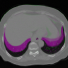

Refer to caption

Figure 4: Visual validation of proposed Conv2Warp method on brain dataset. 1stsuperscript1𝑠𝑡1^{st} column: Target image with source mask, 2ndsuperscript2𝑛𝑑2^{nd} column: target image with deformed (transformed) mask, 3rdsuperscript3𝑟𝑑3^{rd} column: Target image with target mask, and last column: magnitude of predicted deformation field. Grey matter (GM) and white-matter (WM) areas are marked by green and magenta borders and yellow borders, respectively.

In Fig. 3 Conv2Warp without (λ=0𝜆0\lambda=0) regularization and with (λ=0.001𝜆0.001\lambda=0.001) regularization are shown in 4th and 5th columns respectively and their corresponding DVF magnitudes in 6th and 7th columns, respectively. It can be observed that the unconstrained loss function results in some unrealistic deformations (red rectangular regions in 4th column) while a more realistic deformations are visible for the constrained loss proposed in Conv2Warp (5th column). A smooth deformation can be seen in the magnitude image of the DVF uregdelimited-∣∣subscriptu𝑟𝑒𝑔\mid\textbf{u}_{reg}\mid (7th column). Colour overlay images show a large improvement in the alignment of source images Issuperscript𝐼𝑠I^{s} with the target images Itsuperscript𝐼𝑡I^{t} (3rd column) with Conv2Warp method (5th column). Fig. 4 shows the results on T1 MRI test datasets which were first rigidly aligned to MNIspace and then co-registered using Conv2Warp. It can be observed that Conv2Warp handles different magnitudes of non-linear deformations.